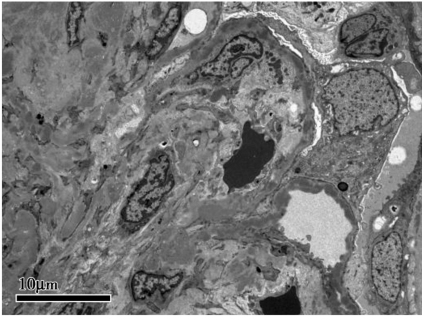

肾活检示免疫荧光:C3(+++),余阴性,系膜区、毛细血管壁颗粒样沉积(图1)。光镜下可见24个肾小球,肾小球系膜细胞和基质中重度弥漫增生,广泛插入,基底膜增厚,双轨征形成,系膜区、内皮下嗜复红蛋白沉积;肾小管上皮空泡及颗粒变性,灶状萎缩;肾间质灶状淋巴和单核细胞浸润伴纤维化;小动脉管壁增厚;符合膜增生性肾小球肾炎(MPGN)(图2)。电镜下肾小球系膜细胞和基质中度增生,广泛插入,基底膜增厚,上皮下、基底膜内、内皮下、系膜区均可见电子致密物沉积,上皮足突广泛融合(图3);符合MPGN。结合患者免疫荧光结果,最终诊断为C3肾小球肾炎。

图3 MPGN型C3肾小球肾炎:系膜区和内皮下电子致密物沉积,上皮细胞足突节段性融合(电镜×4 000)